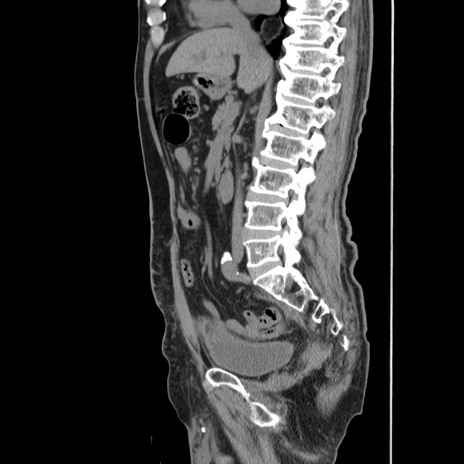

症例24(矢状断像)

【症例】80歳代男性

【主訴】左側腹部痛、嘔吐

【現病歴】本日早朝より左腹部に痛みあり。昼頃嘔吐認めたため、救急要請。

【既往歴】直腸癌(Mile手術)、胆摘

【身体所見】意識清明、BT 35.9℃、BP 221/93mmHg、SpO2 97%(RA) 、腹部:左ストーマ周囲に限局性の腹部膨隆あり。 膨隆部自発痛・圧痛あり・軟。

【データ】WBC 7700、CRP 0.09